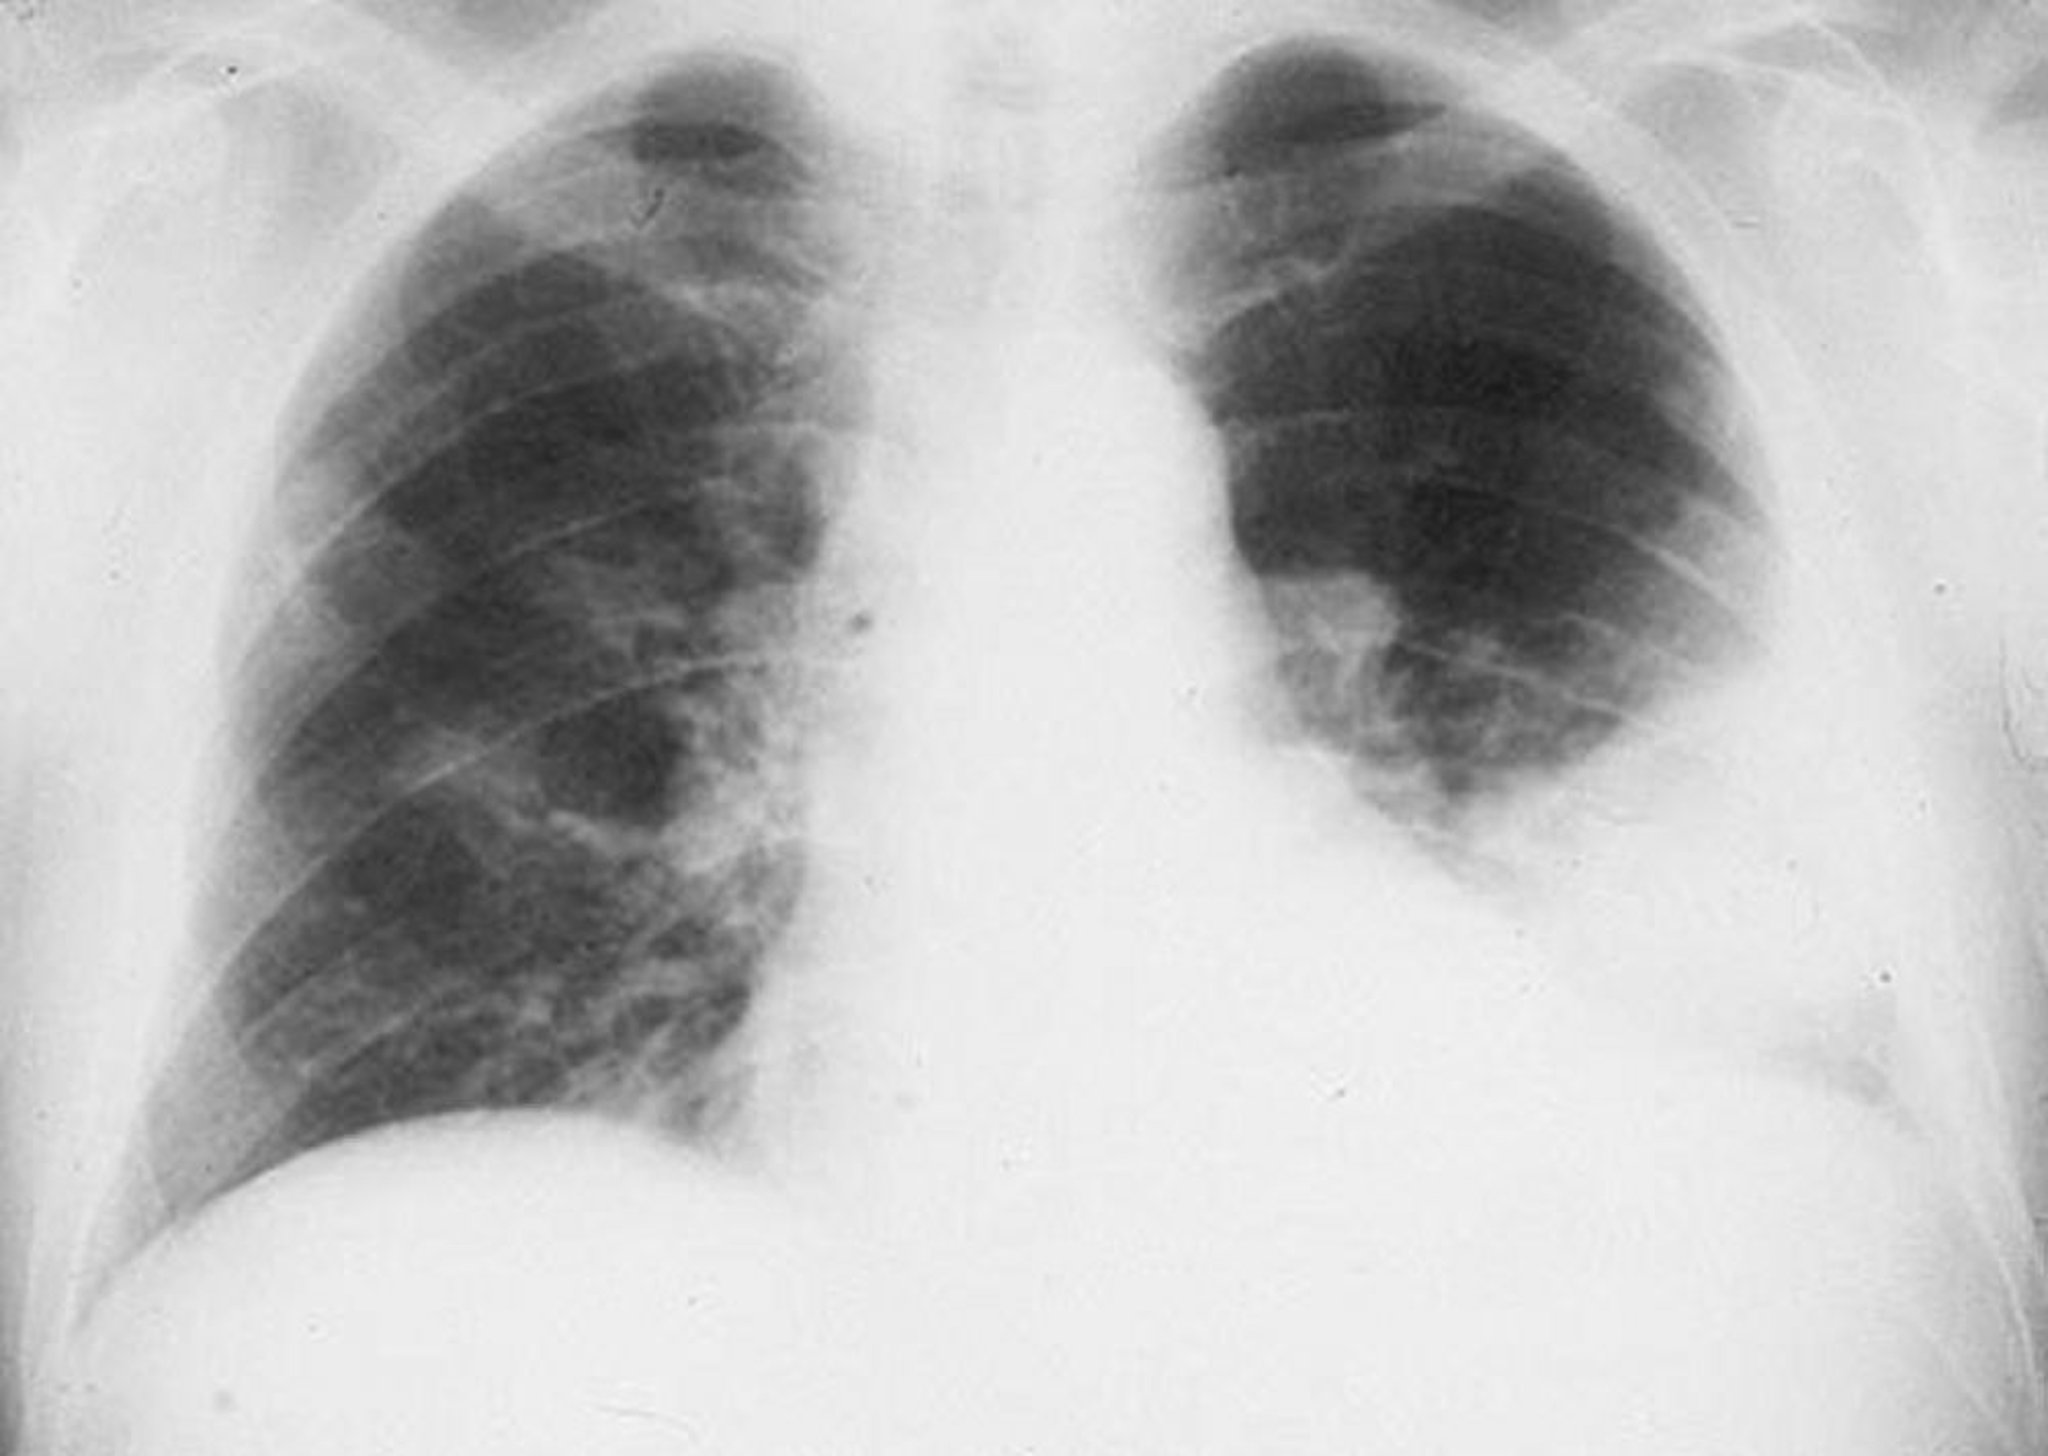

Infiltrado en el lóbulo pulmonar inferior izquierdo

Infiltrado alveolar en el lóbulo inferior izquierdo en un varón con neumonía bacteriana.

By permission of the publisher. De Roberts R. In Atlas of Infectious Diseases: Pleuropulmonary and Bronchial Infections. Publicado por GL Mandell (series editor) y MS Simberkoff. Philadelphia, Current Medicine, 1996.